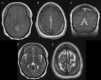

The archetypal imaging characteristics of meningiomas are among the most stereotypic of all central nervous system (CNS) tumors. In the era of plain film and ventriculography, imaging was only performed if a mass was suspected, and their results were more suggestive than definitive. Following more than a century of technological development, we can now rely on imaging to non-invasively diagnose meningioma with great confidence and precisely delineate the locations of these tumors relative to their surrounding structures to inform treatment planning. Asymptomatic meningiomas may be identified and their growth monitored over time; moreover, imaging routinely serves as an essential tool to survey tumor burden at various stages during the course of treatment, thereby providing guidance on their effectiveness or the need for further intervention. Modern radiological techniques are expanding the power of imaging from tumor detection and monitoring to include extraction of biologic information from advanced analysis of radiological parameters. These contemporary approaches have led to promising attempts to predict tumor grade and, in turn, contribute prognostic data. In this supplement article, we review important current and future aspects of imaging in the diagnosis and management of meningioma, including conventional and advanced imaging techniques using CT, MRI, and nuclear medicine.